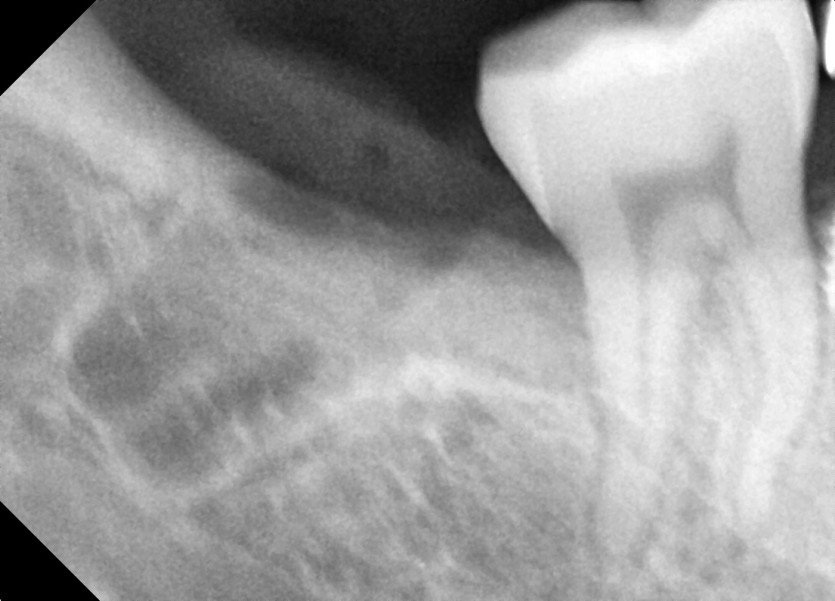

#48 사랑니 발치

구강 외과 전문의가 당일 발치했습니다.